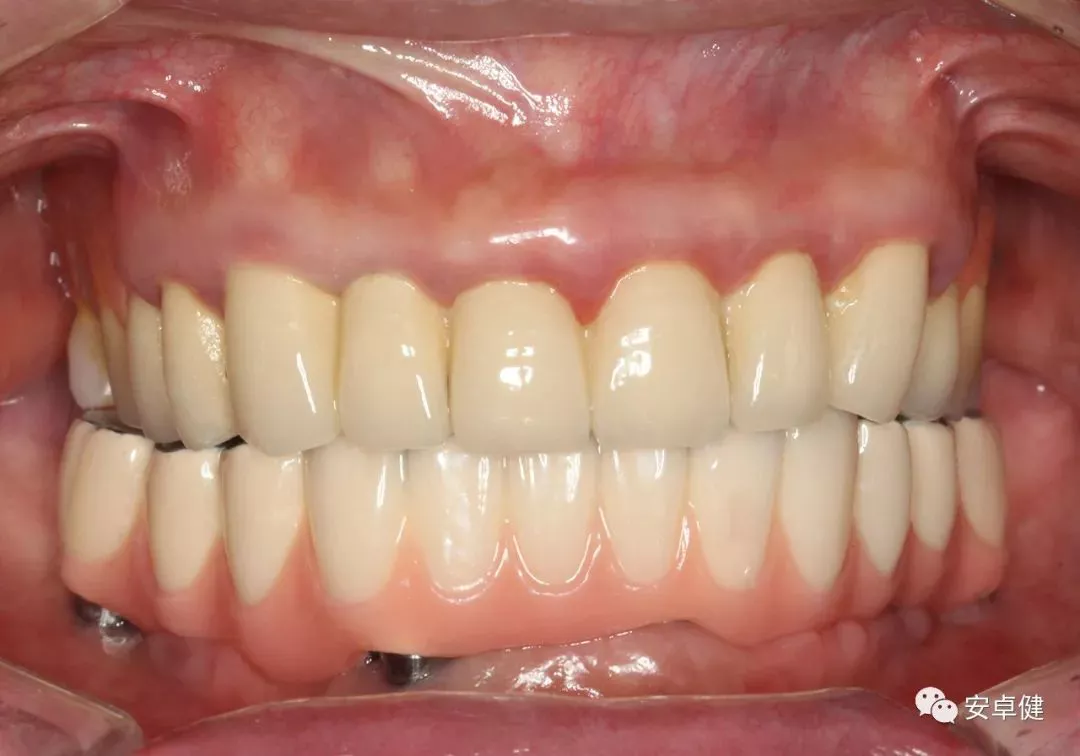

戴最终修复体正面咬合照

▷ 永久修复

患者术后16个月:

• 于口内试戴原厂纯钛切削一体式桥架,并检查前牙排蜡外形及后牙咬合关系;

• 聚合瓷烤塑制作最终修复体;

• 为减少牙面磨耗,于后牙区制作360度防裂纯钛金属带;

• 试戴满意后,二级螺丝加力至15N;

• 特氟龙封闭螺丝孔,光固化复合树脂封闭上方螺丝通道,完成最终固定式种植义齿修复;

• 修复体外形能够正确恢复面下1/3高度及侧貌;

• 患者可获得较为稳定的咬合关系,并满足其咀嚼功能的需求;